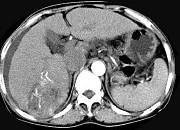

问题 女性,55岁,曾患乙肝,肝硬化多年,右上腹胀痛1月余,CT检查如图所示,最可能的诊断是 ( )

选项 A.肝硬化腹水、下腔静脉血栓形成 B.肝硬化腹水、胆管细胞癌 C.肝硬化腹水、肝癌并下腔静脉癌栓 D.肝硬化腹水、肝脓肿 E.肝硬化腹水、肝血管瘤

答案 C